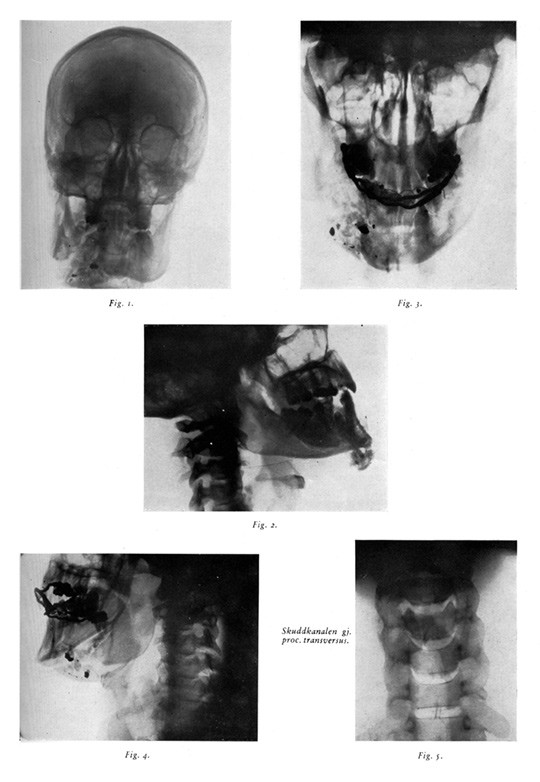

Pasienten hadde en innskuddsåpning i nakken vel en tommelfingerbredd til venstre for processus spinosus på C3. Utskuddsåpningen var et par fingerbredder til venstre for hakespissen. Åpningen var temmelig stor og opprevet med svulne, betente sårrander. Det var en komminutt faktur av mandibula, og en rekke tenner manglet. Ved inspeksjon av munnhulen var det en moderat submukøs hevelse i venstre sublingvale region. Det var ingen tegn til lesjon av større kar, og ved nevrologisk undersøkelse var det ingen tegn til skade av hjernenerver, ryggmarg eller noen av de spinale nervene.

Det står videre: «I samarbeid med Rikshospitalets daværende tannlæge, dr. Ruud, lyktes det uten særlig vanskeligheter i lokalanestesi å reponere de disloserte fragmenter av kjeven på en ganske tilfredsstillende måte». Man avsto fra å forsøke å fjerne alle spredte fragmenter av tenner og metallstykker «idet man antok at disse bedre ville demarkere og støtes ut spontant». Underkjeven ble fiksert med bøyler på gjenværende tenner. Forløpet var ukomplisert, bortsett fra en submandibulær abscess. «Sekvester, tannstumper og fremmedlegemer støtes ut, og det kom til god konsolidasjon av kjevefrakturen» (1).

Røntgen av cervikalcolumna ble først gjort i forbindelse med en kontroll i juni 1945 da pasienten ble demonstrert i Det norske medicinske Selskab (fig 2). Bildet «viste at prosjektilet hadde passert gjennom prosessus transversus for C. IV. medialt for a. vertebralis». Gade skrev videre: «Kasus frembyr som nevnt ikke noen synderlig kirurgisk interesse. Han som skjøt traff dårlig, det er hele forklaringen. Følger en imidlertid i tankene prosjektilets bane gjennom nakke, hals og kjeve og erindrer seg de overordentlig tallrike muligheter for alvorlige inntil fatalt forløpende lesjoner som har vært til stede, må en medgi at pasienten – også det feilaktig anbrakte skudd tatt i betraktning -, har vært overordentlig heldig» (1).

I kasuistikken står det videre at ved demonstrasjonen i Det norske medicinske Selskab befant pasienten seg «fullstendig vel og frembød absolutt intet mén etter hendelsen hverken psykisk eller somatisk, bortsett fra de manglende naturlige tenner og en helt lokal hypestesi av underleppen til venstre, svarende til utbredningsgebetet for n. mentalis s. (n. alveolaris inf.)» (1).